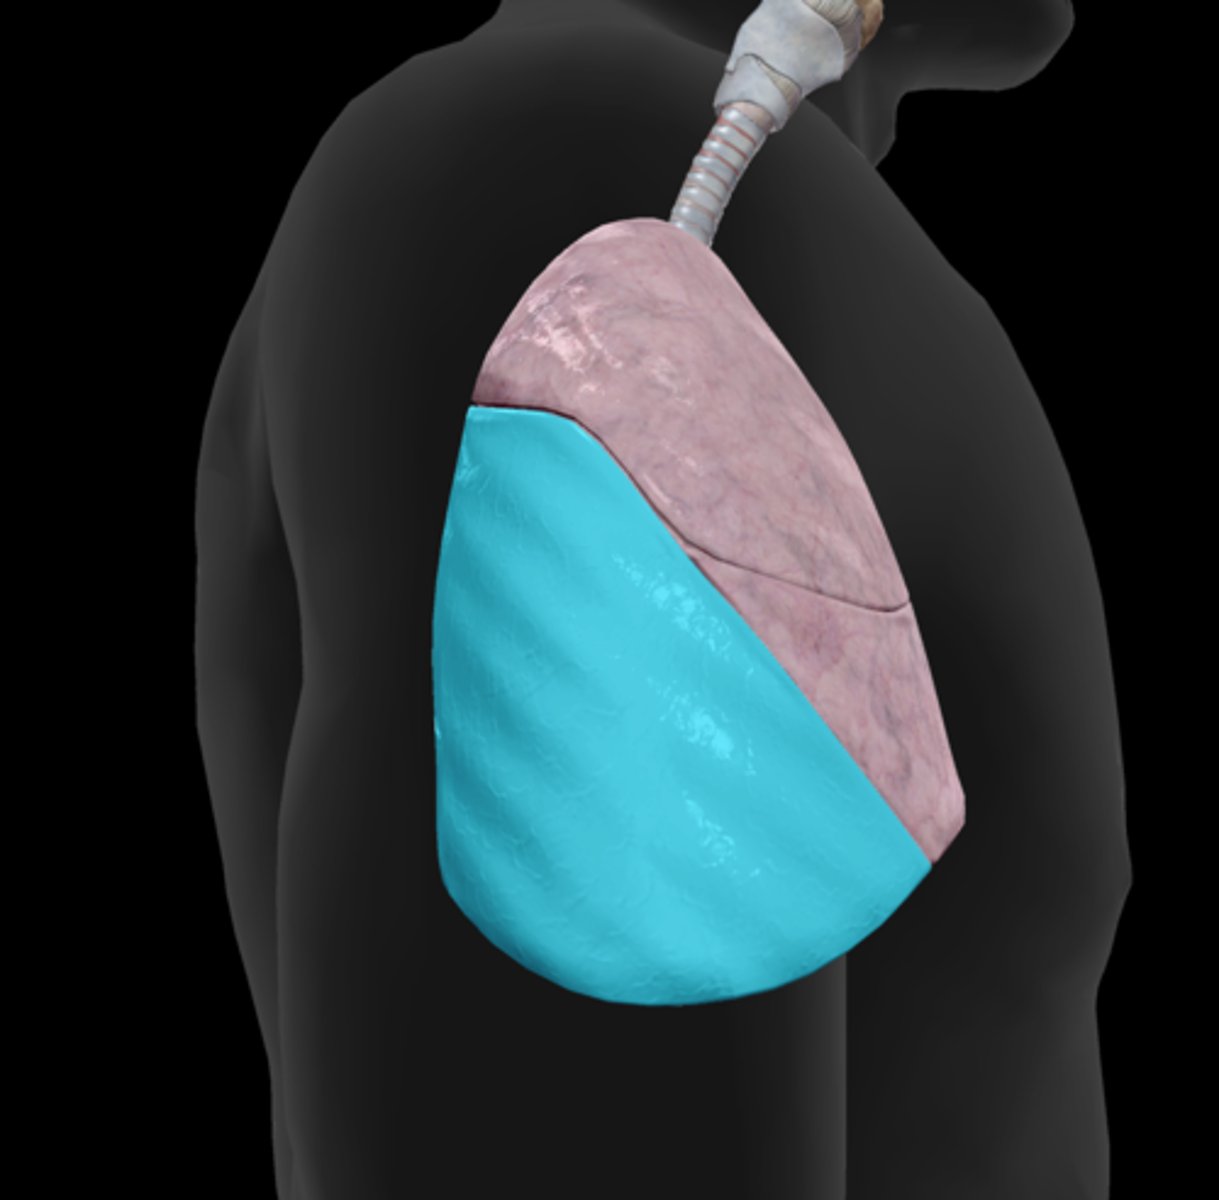

Superior lobe

Middle lobe

Inferior lobe

Horizontal fissure

Oblique fissure